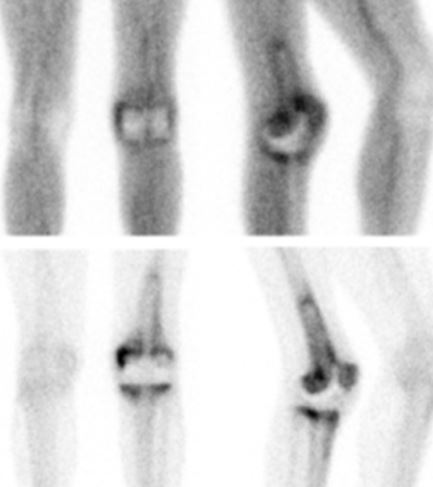

Nuclear scans can aid in detecting loosening and infection. If infection is suspected, aspiration of the fluid is mandatory to attempt to confirm the diagnosis and identify the micro-organism.